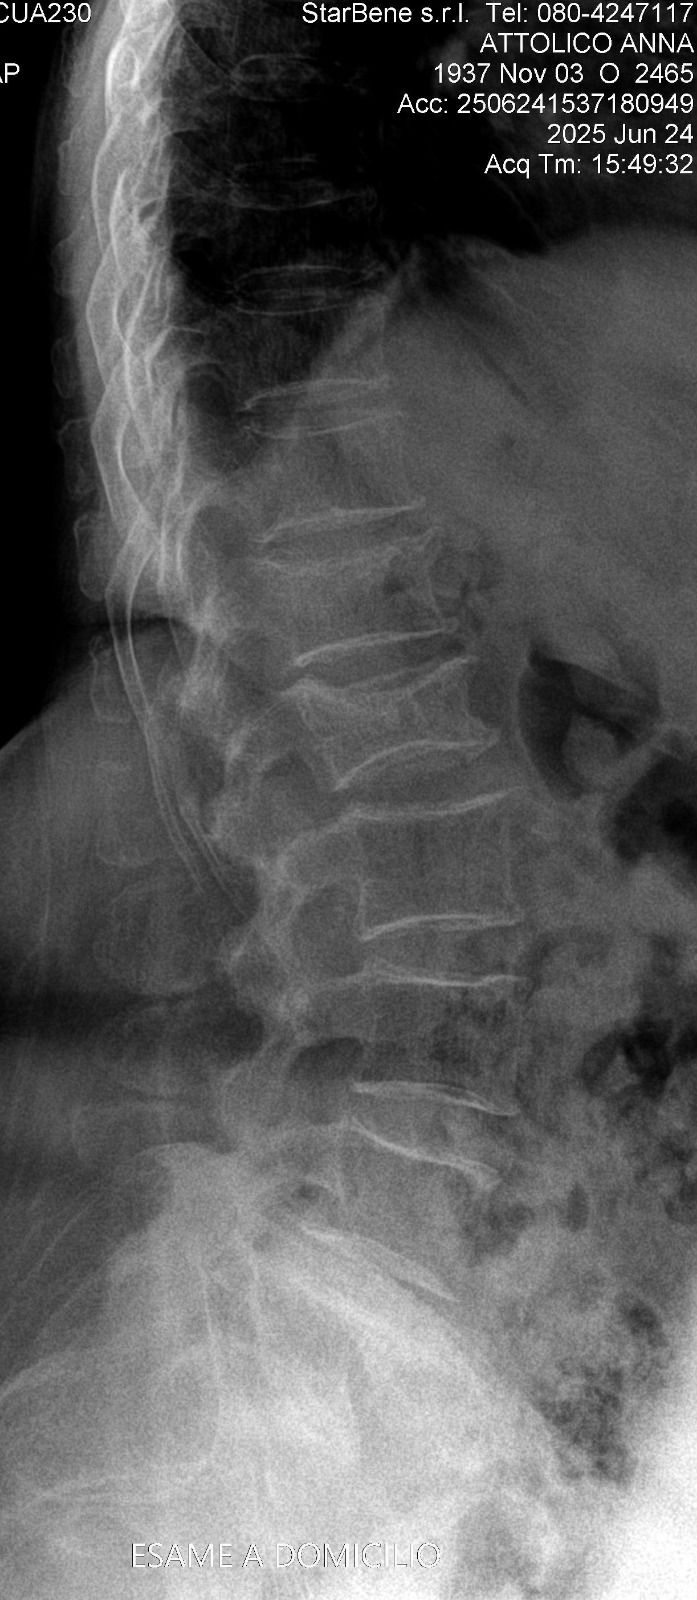

Foto e video